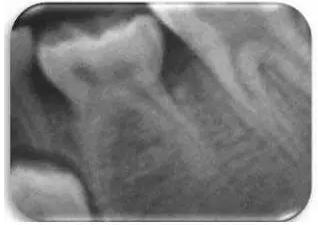

發(fā)育不全被定義為乳磨牙分叉下方的骨嵴沒有鈣化的跡象。采用Demirjian方法將相應(yīng)的前磨牙發(fā)育分為8個階段。對應(yīng)牙齒發(fā)育缺失的“0期”已被作者另外考慮(圖2)。

文獻直達|一項西班牙的研究:低位乳磨牙的發(fā)生頻率、程度、牙根吸收和前磨牙發(fā)育不全情況\

圖2 影像學(xué)觀察到的由左側(cè)第二乳磨牙的低牙合導(dǎo)致的前磨牙發(fā)育不全。